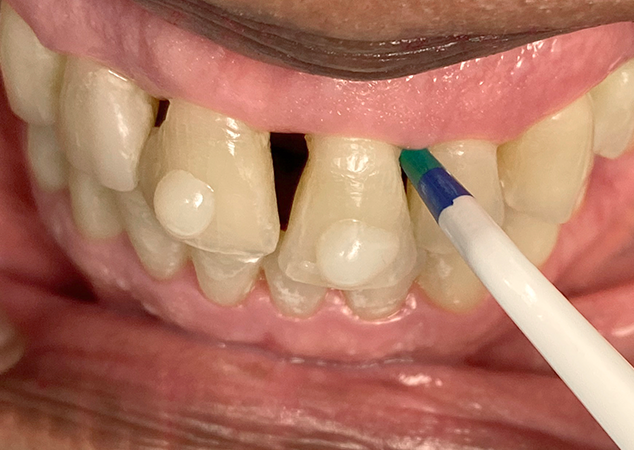

Lors de la consultation initiale, il est important de mesurer les embrasures gingivales à l'aide de la jauge de triangle noir Bioclear (Fig. 4). Ensuite, effectuez un essai de matrice pour évaluer l'exactitude de la mesure et la sélection ultérieure de la matrice destinée à combler l'embrasure (Fig. 5). L'expérience du clinicien et un œil attentif à l'esthétique guident la sélection finale de la matrice la mieux adaptée pour recréer le profil d'émergence approprié. Dans ce cas, nous avons convenu avec le patient de combler les embrasures de 13 à 23 et d'utiliser des matrices de triangle noir Bioclear pour réaliser des facettes à 360° afin de remodeler et de reconstruire les profils faciaux et incisaux.

Lors de la consultation initiale, la correspondance des teintes est obtenue à l'aide de pastilles de composite placées et polymérisées sur la surface vestibulaire des incisives centrales. Chaque embrasure est mesurée et enregistrée à l'aide de la jauge à triangle noir Bioclear.

Les essais de matrices agissent comme un wax-up pour projeter l'apparence de la restauration finale. Il est crucial de prendre en compte les limites de cette méthode pour la gestion des attentes du patient. Un triangle noir résiduel est anticipé entre les deux incisives centrales supérieures.